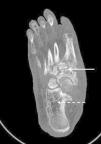

La osteoneuropatía de Charcot es una entidad potencialmente destructiva que ocurre asociada a las afecciones que causan pérdida de sensibilidad en los pies, siendo la neuropatía periférica secundaria a la diabetes mellitus la causa más común, con una incidencia entre el 0,1 y el 5%1,2. No obstante, otras condiciones patológicas podrían causar el pie de Charcot, como es la neurosífilis, la esclerosis múltiple, la poliomielitis, la deficiencia de ácido fólico y vitamina B12, la infección por VIH y el abuso crónico de alcohol entre otras1,2. Los datos publicados de prevalencia e incidencia de la enfermedad indican que a menudo no se diagnostica entre los dependientes del alcohol, con cifras que van del 0,4 al 13%, datos similares a los pacientes diabéticos1,2. La deformidad del «pie en mecedora» es su manifestación tardía y más grave1,2. Presentamos el caso de un paciente varón en su quinta década de vida, no diabético y consumidor crónico de 350g de alcohol/semana. Ha ingresado en nuestro centro por úlceras de ambas piernas. A la anamnesis ha explicado cuadro de 12 meses de evolución de aparición de edemas, úlceras y sensación ardiente de piernas, así como hinchazón progresivo del pie derecho, sin traumatismo previo. La exploración ha evidenciado úlceras supurativas y pie derecho deformado plano convexo con eritema y ulceración plantar (rocker-bottom foot o pie en mecedora). Se ha realizado tomografía computarizada (fig. 1), que ha demostrado afectación difusa con desestructuración y remodelación ósea del mesopié tarso-metatarsiana y escafo-cuneiformes (flecha blanca recta), y áreas radiolúcidas compatibles con osteopenia por desuso (flecha blanca punteada). Se ha realizado electromiografía, que ha demostrado neuropatía periférica sensorial. Ante los hallazgos clínico-epidemiológicos, radiológicos y neurológicas se ha diagnosticado de osteoneuropatía de Charcot. El síndrome de dependencia del alcohol es una enfermedad social crónica, siendo la polineuropatía periférica su complicación neurológica más frecuente, y está relacionada con deficiencias nutricionales (malabsorción de tiamina —vitamina B1—) y la neurotoxicidad directa del etanol como presumibles factores de riesgo para desarrollar el pie de Charcot. Los factores desencadenantes y la patogénesis del pie de Charcot no están claros, pero probablemente se asocia con factores mecánicos y vasculares secundarios a la neuropatía periférica sensorial y autonómica. En la fase aguda es esencial el diagnóstico diferencial con celulitis, osteomielitis o trombosis venosa profunda. El pronóstico depende de la detección precoz, y la respuesta al tratamiento depende del estadio en el momento del diagnóstico. El tratamiento inicial —como es el caso que presentamos—, además del antibiótico ajustado —en caso de infección asociada— y las curas de enfermería, consiste en la inmovilización y descarga del pie mediante yeso completo, para minimizar el edema y detener la progresión de la enfermedad. En una segunda fase, se utilizan los calzados hechos a medida3,4. Si fracasa, en los pies con deformidad severa, se puede practicar una cirugía —para lograr un pie plantígrado y evitar que las exostosis provoquen presión en la piel y por lo tanto úlceras, una cirugía de tendones para restaurar el equilibrio muscular o la reconstrucción electiva para dejar un pie funcional y prevenir la amputación—3,4, que, en nuestro caso, ha sido rechazada por el propio paciente.